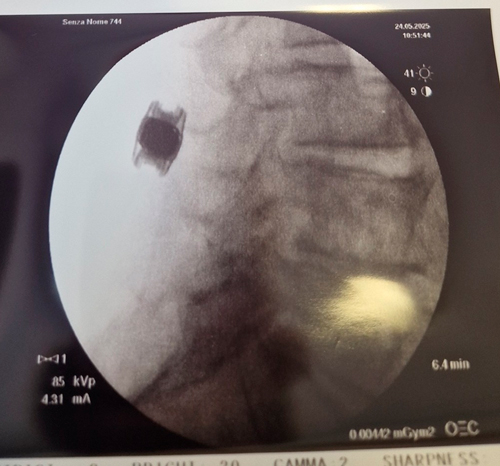

Intervento chirurgico eseguito:

Introduzione di dispositivo interspinoso lombare L3-L4 per via percutanea

Radiografia post-operatoria